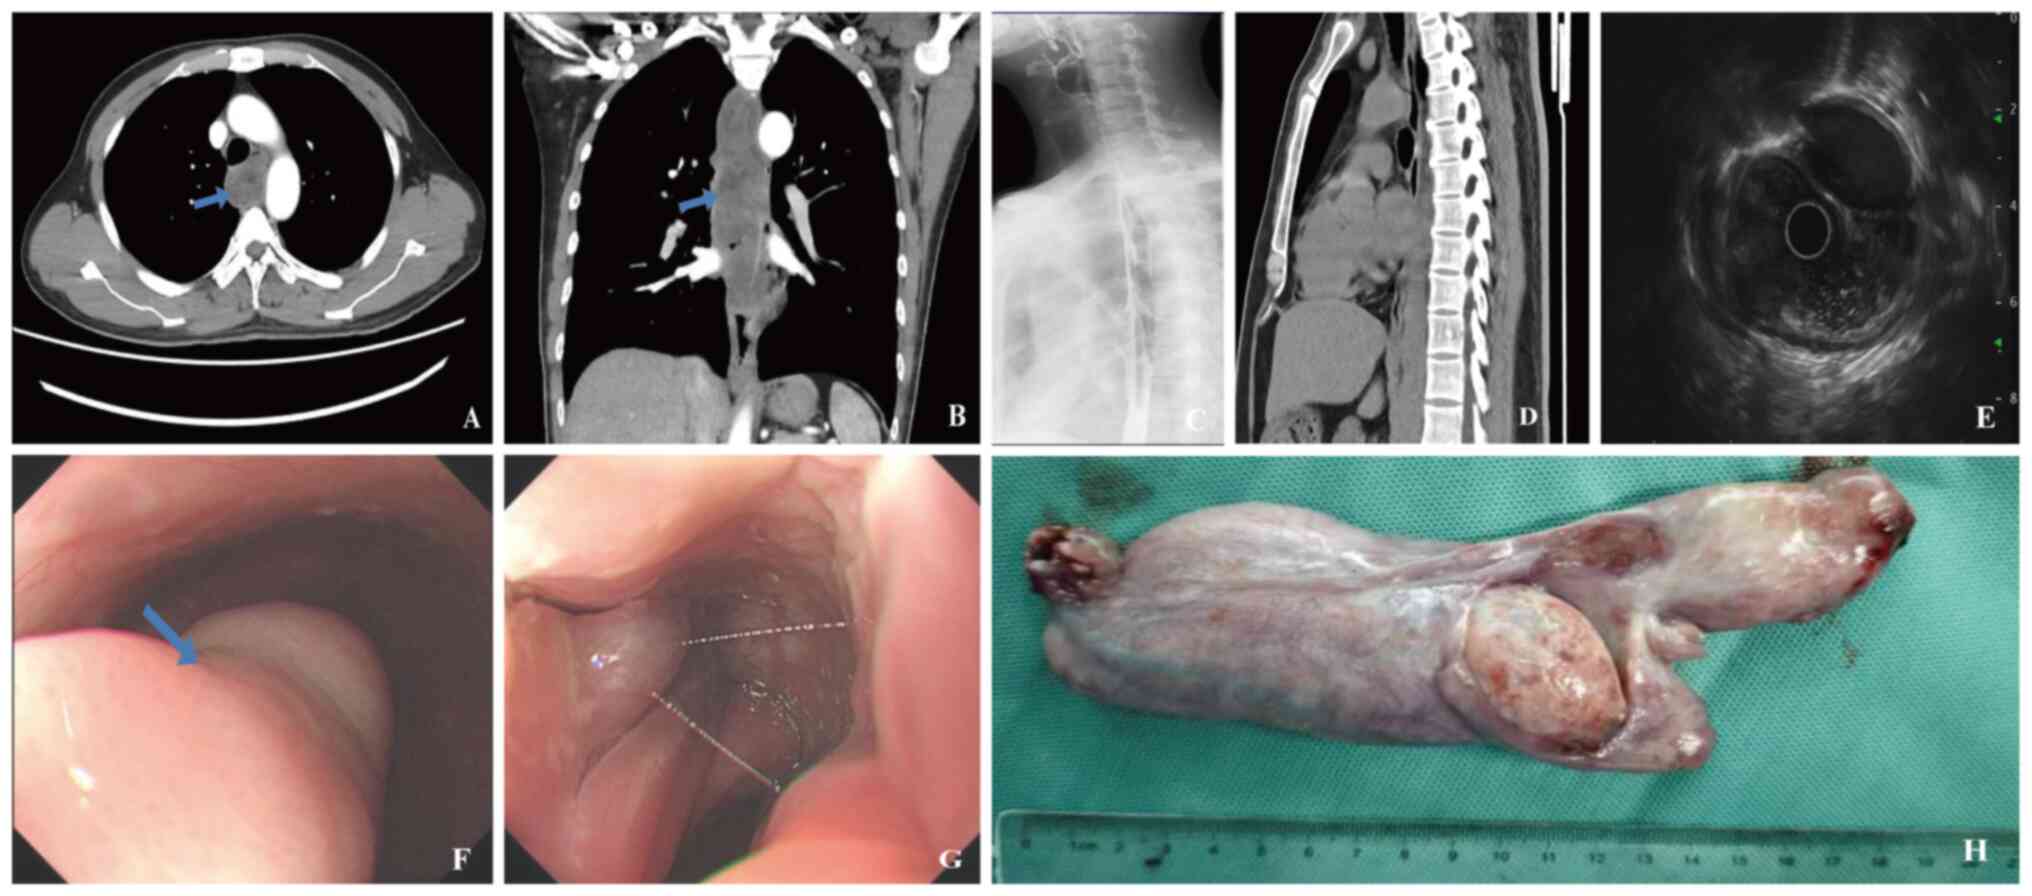

Discussion on surgical approaches for giant, well‑differentiated liposarcomas of the esophagus: Report of two cases

Giant liposarcoma of the esophagus is an exceedingly rare esophageal tumor with complex treatment options. This study investigated the treatment modalities and reported on the clinical outcomes of two cases involving giant, well‑differentiated liposarcoma of the esophagus, providing a reference for the management of similar cases. Both tumors measured >20 cm in length and had diameters exceeding 4 cm; one case exhibited a lobulated appearance with visibly expanded blood vessels on its surface. Following discussions within a multidisciplinary team, under general anesthesia with tracheal intubation, the endoscopy team conducted endoscopic submucosal dissection, collaborating with the thoracic surgery team to manage potential bleeding risks. Both patients successfully underwent endoscopic tumor removal with postoperative pathology confirming the presence of well‑differentiated liposarcoma and no observed complications. For patients with giant and complex well‑differentiated liposarcomas, endoscopic dissection in conjunction with multidisciplinary collaboration represents a safe and effective treatment option, ensuring complete tumor removal while minimizing surgical trauma and enhancing patient prognosis.